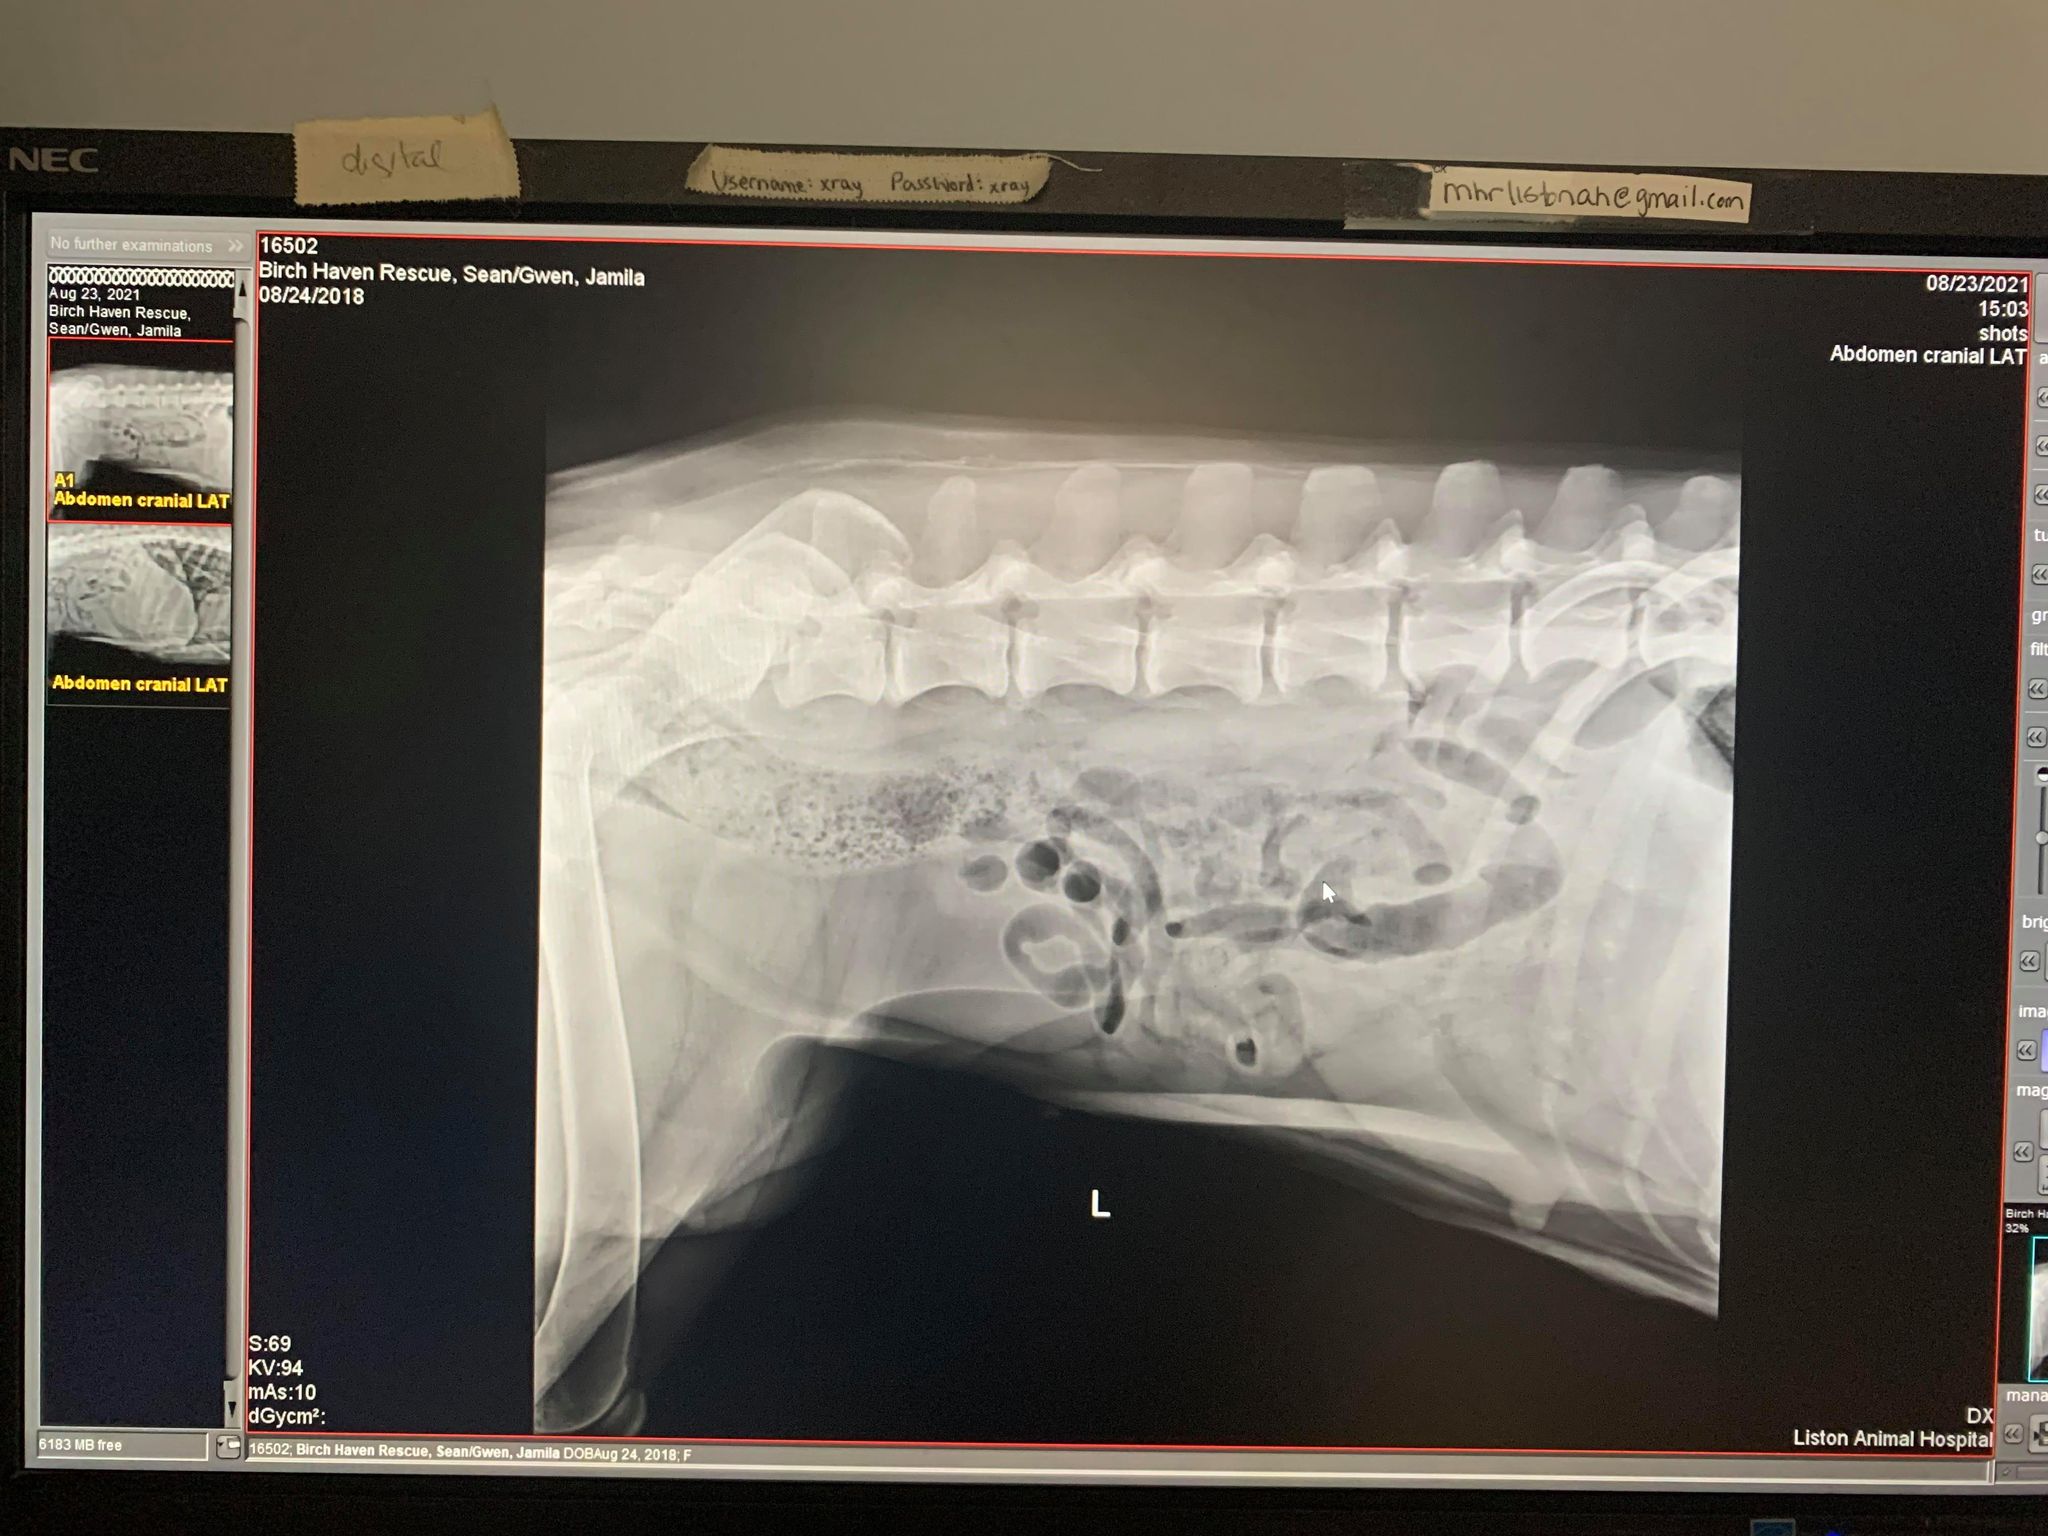

Miss Jamila!

A copy of her two x-rays.

Please assist us in surrounding her with a village of support and love!